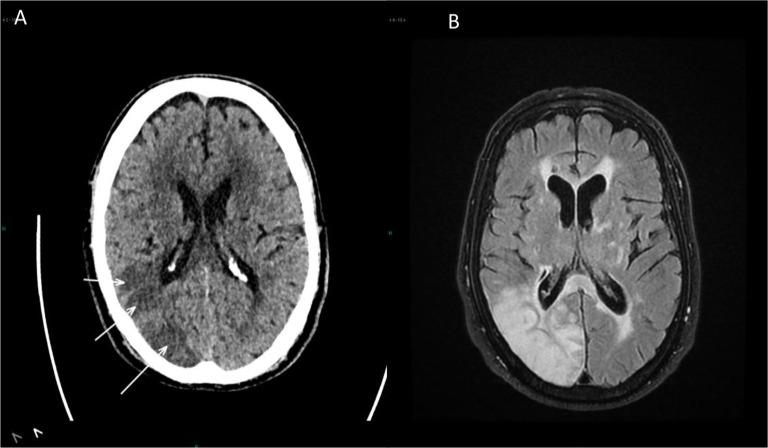

Papillary Fibroelastomas are rare, primary cardiac tumors. They are typically diagnosed as an incidental finding but can also present as thrombo-embolic events. We present the case of 78-years- old man who presented to emergency room with a cerebrovascular event (CVE). Transesophageal echocardiography (TEE) revealed e presence of a mass on the aortic valve. Intra-operatively, two masses where found: one was highly mobile attached to left ventricular (LV) side of the left coronary cusp, another small size mass attached to the non-coronary cusp, and there was suspicion of a mass attached to the mitral valve. The two masses were surgically excised using a right mini-thoracotomy, and histopathological examination confirmed the diagnosis."

乳头状纤维弹性瘤是罕见的原发性心脏肿瘤。它们通常是在偶然检查中被诊断出来,但也可能表现为血栓栓塞事件。我们报告一例78岁男性患者,因脑血管事件(CVE)就诊于急诊室。经食管超声心动图(TEE)显示主动脉瓣上有一个肿块。术中发现两个肿块:一个高度活动,附着于左冠状动脉瓣叶的左心室(LV)侧,另一个小肿块附着于无冠状动脉瓣叶,并且怀疑有一个肿块附着于二尖瓣。通过右胸小切口手术切除了这两个肿块,组织病理学检查确诊。